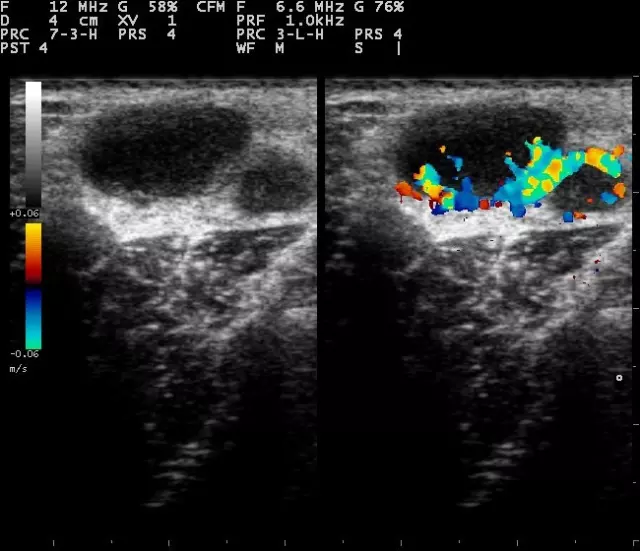

Ultrazvučna dijagnostika i color doppler, usluge su koje vrši POLIKLINIKA JELOVAC D.O.O.